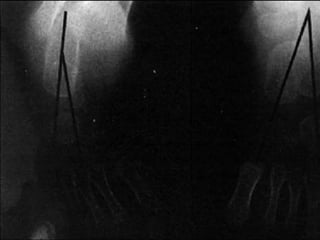

POST OPERATIVE XRAY OF THE SAME CHILD

POST OPERATIVE XRAY

POST OPERATIVE XRAYOF THE SAME CHILD

RADIOLOGICAL FINDINGS

The talo-calcaneal index was measured both preoperatively and post

operatively. The findings are shown below.

Average pre-

operative

Average Post

–operative

Normal values

A.P. 13o

20o

25-40

Lateral 20o

35o

25-50o

T.C. Index 33o

55o

>40o